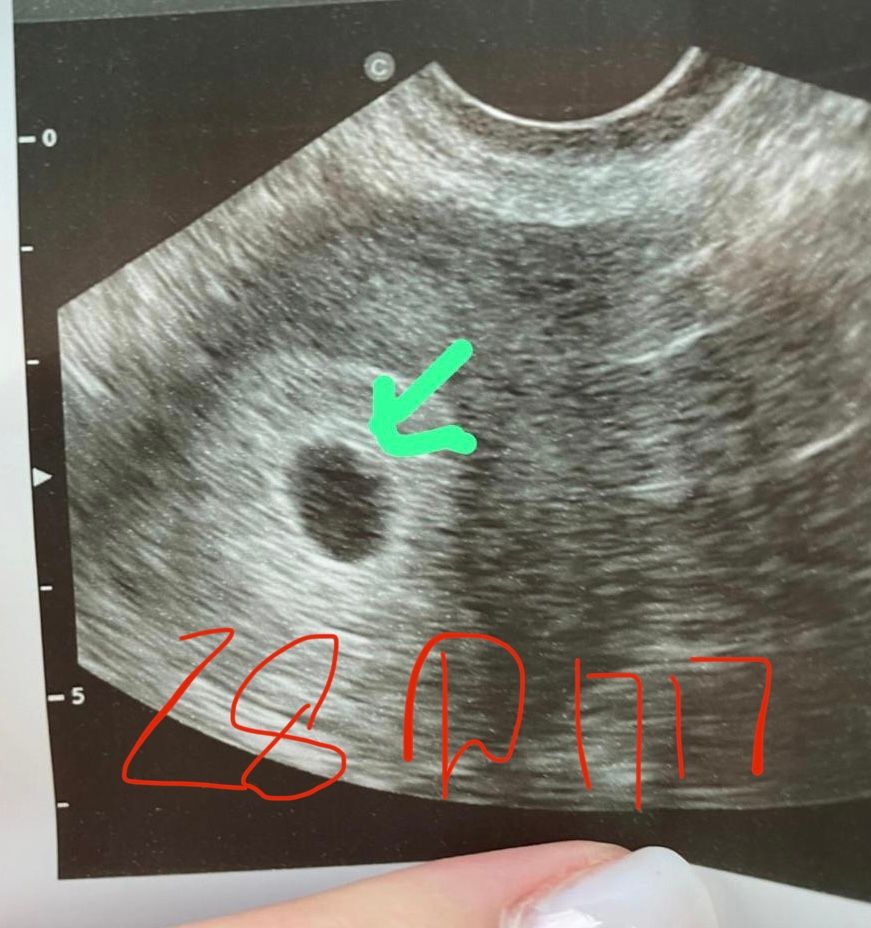

28 дпп пока эмбриона не увидели …

На 31 дпп увидели эмбриончик

Сейчас остаётся только надеяться, у меня тоже на 28 дпп не увидели, а на 29 дпп увидели эмбрион 2 мм и сердцебиение, но к сожалению ни чем хорошим не закончилось, но потом выяснилось что у меня тромбофиллия и надо было всю беременность сидеть на клексане, а мне его на 10 дпп отменили

А в динамике размеры ПЯ не сказали? Вообще по статистике на 28дпп уже находят эмбрион и сб…Но всякое в жизни бывает. Главное не затягивать и мониторить процесс.